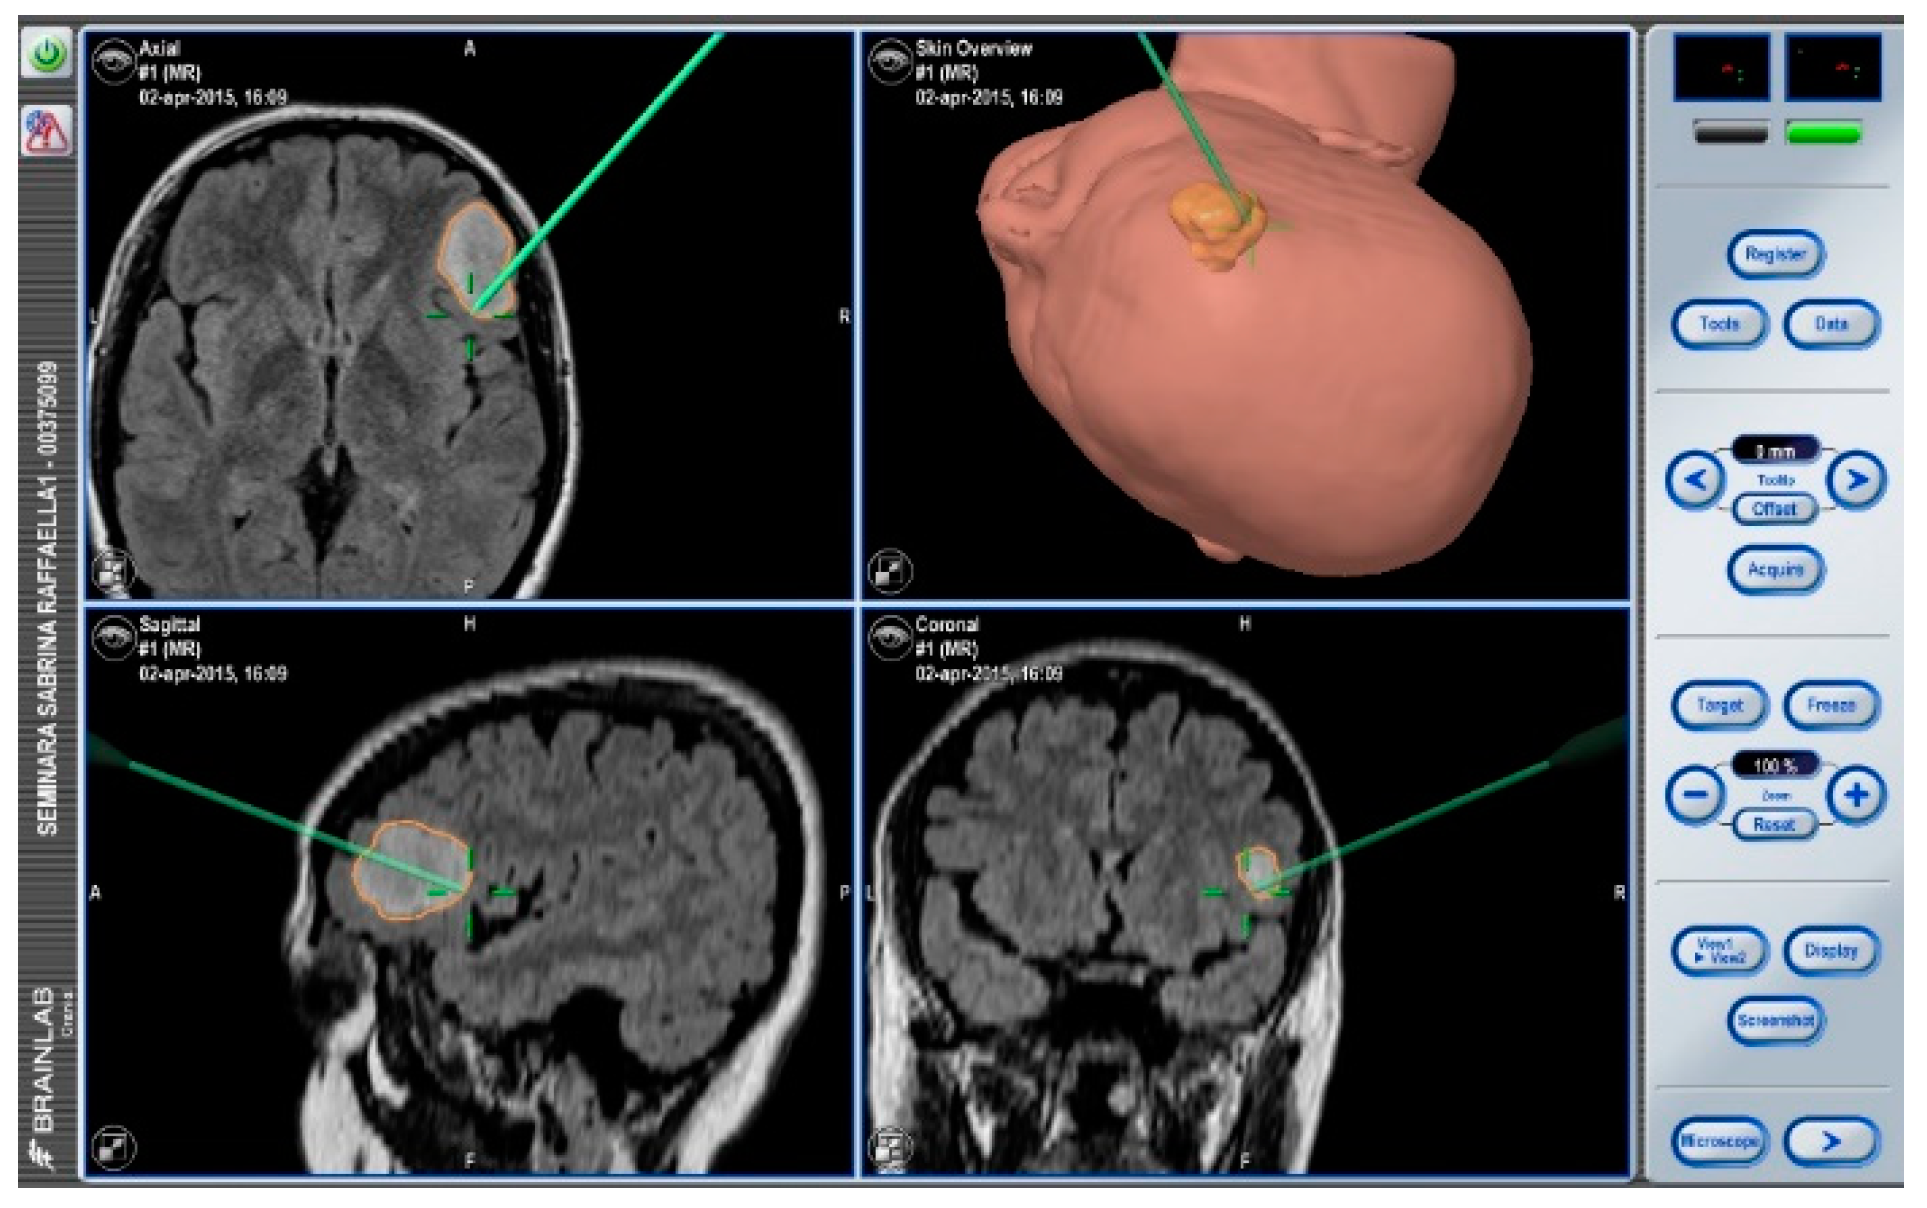

After navigation-guided identification of the tumour boundaries, an “awake” resection was performed and intraoperative identification of Broca’s area (tag 5) with “speech arrest” and inferior fronto-occipital fascicle (IFOF) with transient fonemic paraphasia was reached (tag 8) Figure 2, Figure 3 and Figure 4. Resection was then stopped.

Figure 2. Neuronavigation system adopted at our Institution.

Brainsci 08 00192 g002